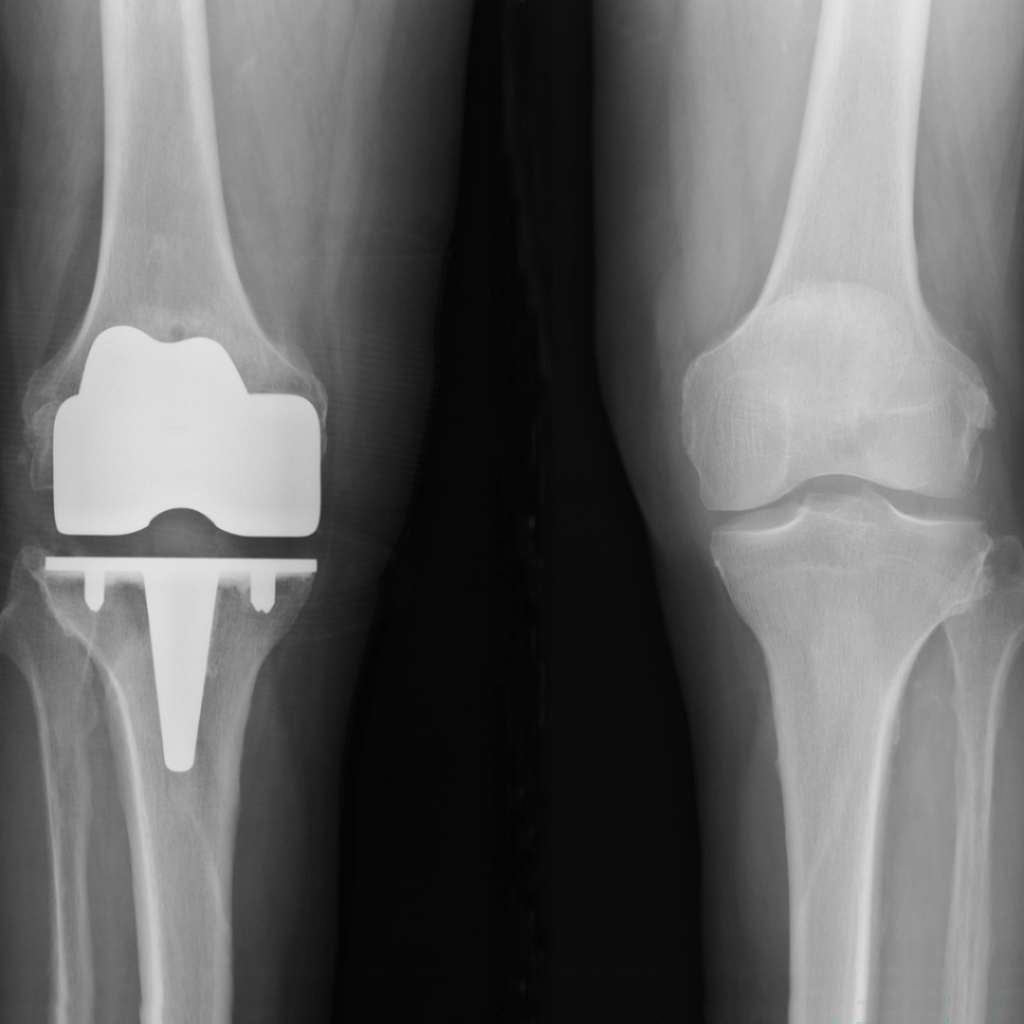

Diz Artroplastisi

Gonatroz, diz eklemindeki kıkırdakların bozulması ve dejenerasyonu nedeniyle ortaya çıkan bir sağlık sorunudur. Gonatroz, diz ağrısı, sertlik, şişlik ve hareket kısıtlılığı gibi semptomlara neden olabilir. Genellikle yaşlı yetişkinlerde daha yaygın olmasına rağmen, her yaştan insanı etkileyebilir.